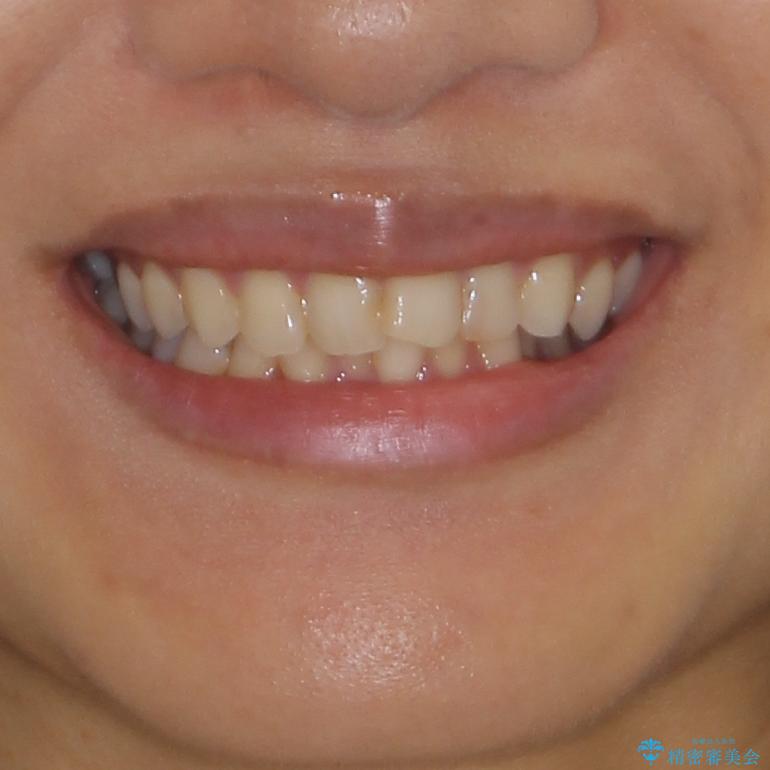

- 前歯のデコボコを気にして来院された患者様です。

IPR(歯と歯の間を削る)によってデコボコが解消するように設計し、インビザラインにより治療を行うこととしました。

下顎善の叢生をもう少し改善したかったのですが、患者様は十分に整ったとのことで治療を終えることになりました。